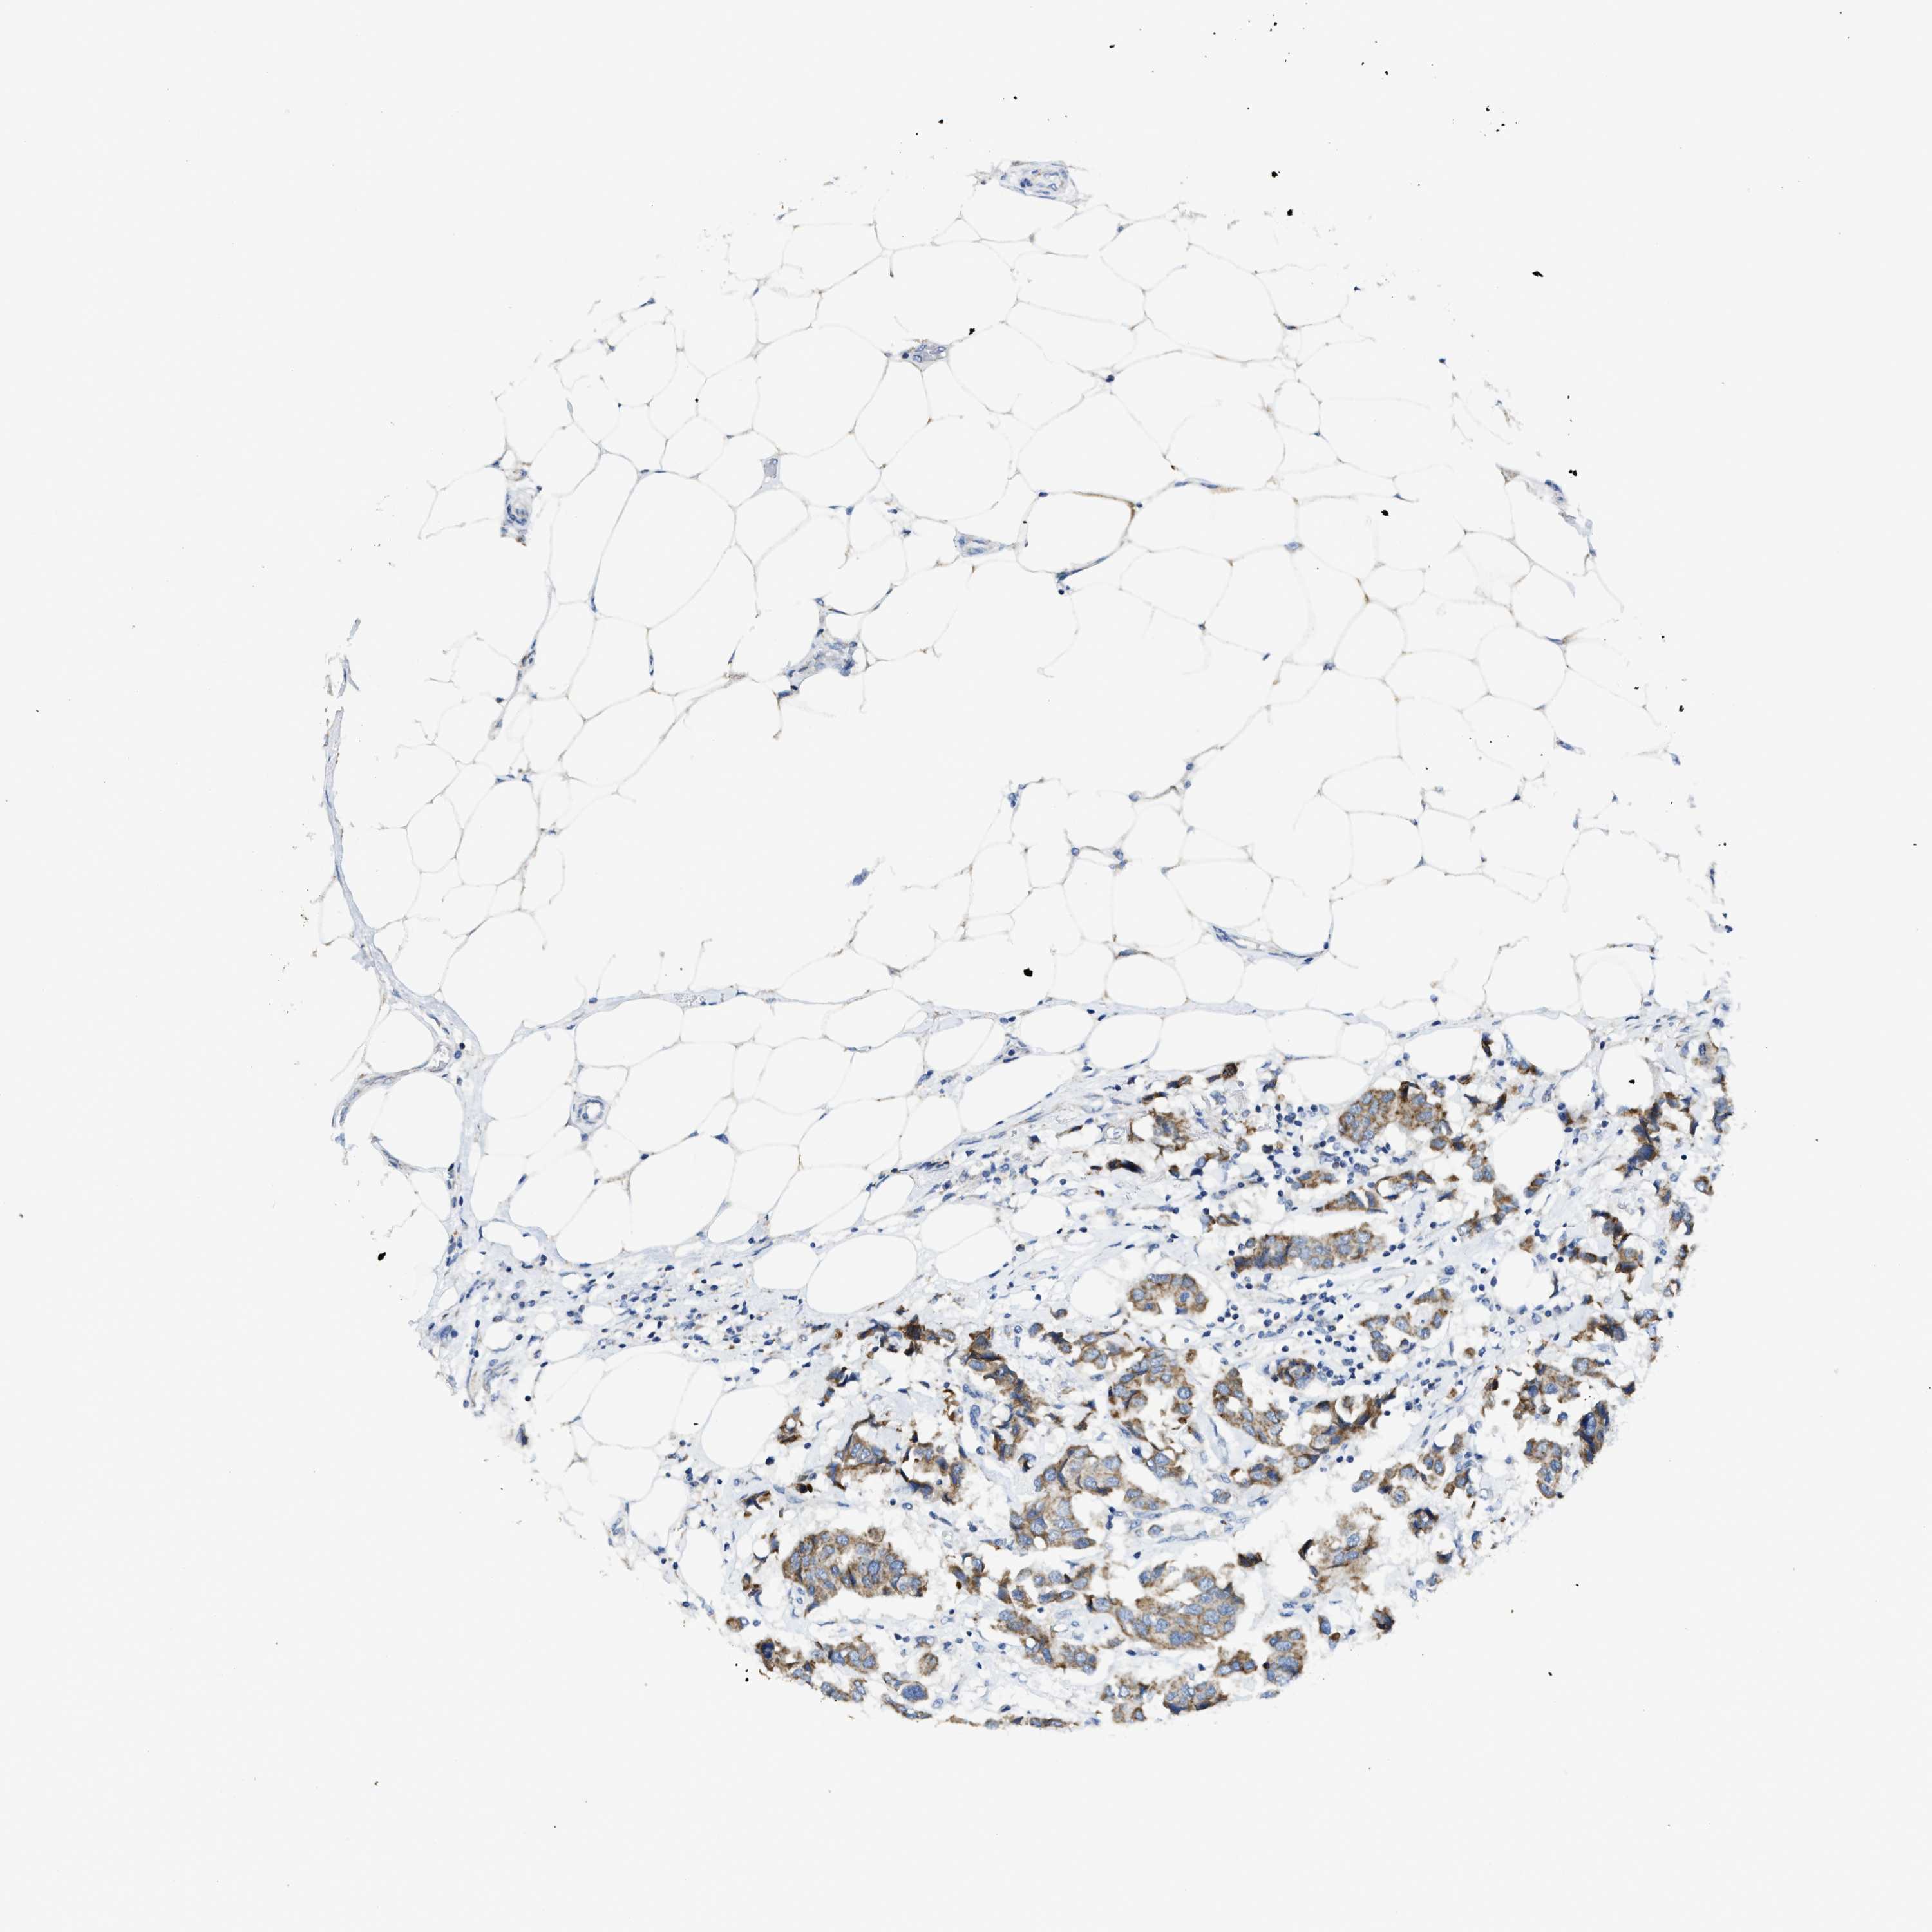

CANCER BREAST CANCER Show tissue menu

BRCA TCGA BRCA VALIDATION PROTEIN EXPRESSION

ANTIBODIES

AND

VALIDATION